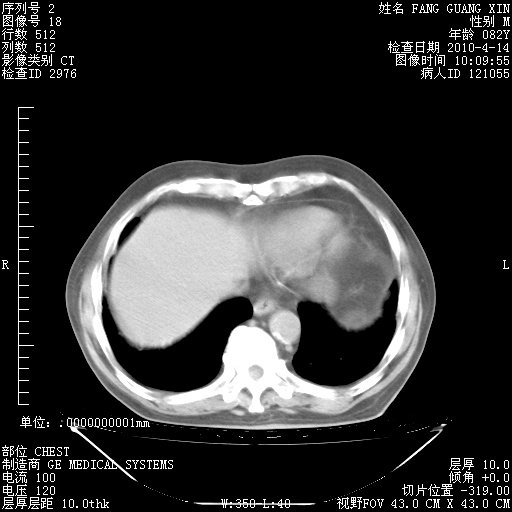

楼主| 发表于 2010-4-28 16:59 | 显示全部楼层

4月28日肺部CT——再次出现类似去年5月9日——透光度降低,(影像科认为)“间质性”改变。

1221483 1 .bmp

1221483 2 .bmp

1221483 3 .bmp

1221483 4 .bmp

1221483 5 .bmp